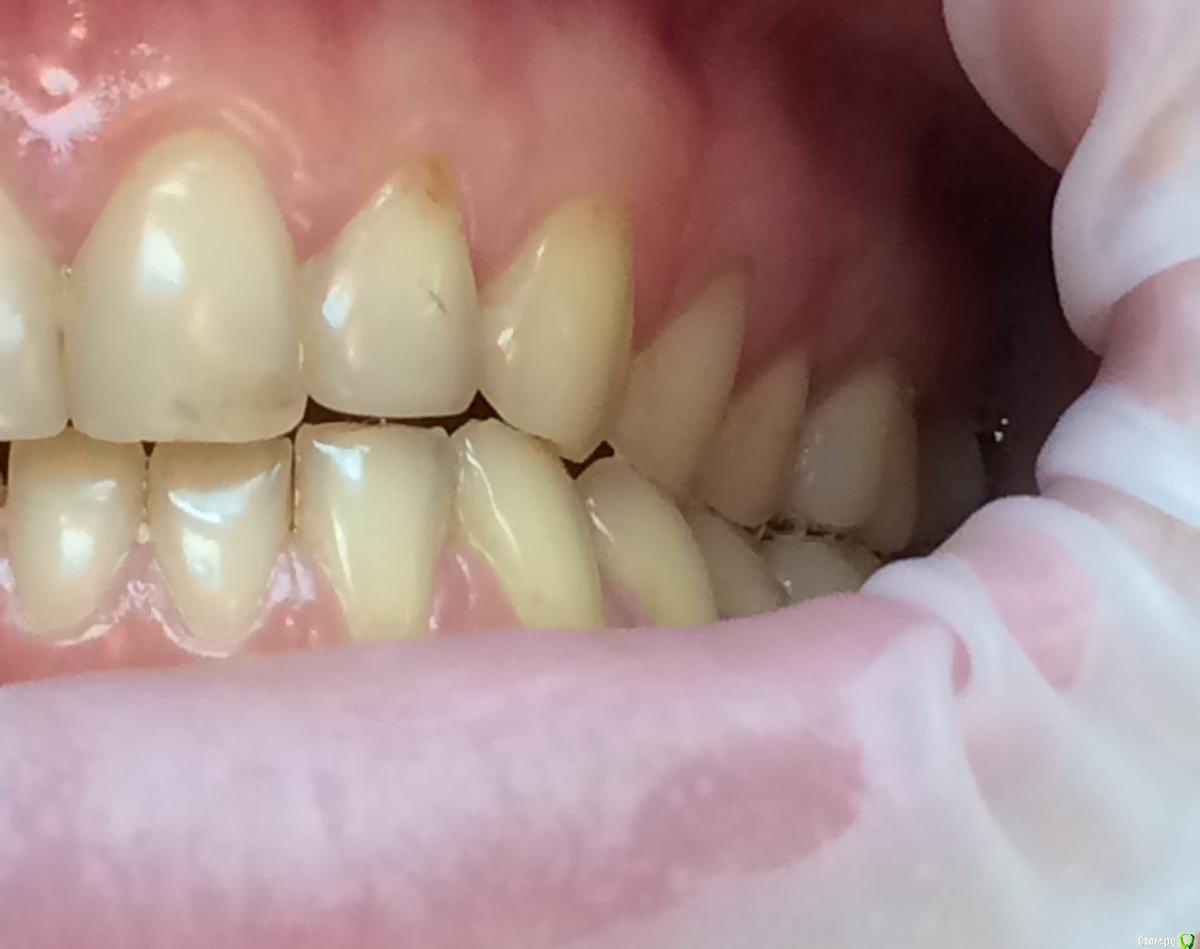

Larnary Опубликовано 28 июля, 2015 Поделиться Опубликовано 28 июля, 2015 (изменено) Добрый день!Ко мне обратилась пациент 1988 гр с жалобой на стираемость зубов и постоянные сколы пломб.Объективно небная поверхность верхних резцов стерта до дентина. Окклюзионная стираемость жевательной группы зубов.Прошу помочь с выявлением причины такой стираемости зубов и оптимальноно метода лечения Изменено 28 июля, 2015 пользователем Larnary Ссылка на комментарий

Bobby Опубликовано 29 июля, 2015 Поделиться Опубликовано 29 июля, 2015 Фасетки стираемости на нёбных поверхностях верхних резцов и вестибулярных поверхностях нижних резцов обусловлены малым оверджетом - недостаточная щель по саггитали, поэтому и будут колоться реставрации, а ткани зубов истираться. Фрадеани про это на своём курсе рассказывал и показывал видео как это диагносцировать и что с этим делать. Что вообще хочет пациентка и на что готова? Эти вопросы лучше сразу решать на первичной консультации, а то делаете диагностики, всё рассчитываете, распинаетесь, а они потом: "ой, я пока не готов/а к такому плану лечения" и всё заканчивается композитной мазнёй в другой клинике. 5 Ссылка на комментарий

zzkz Опубликовано 29 июля, 2015 Поделиться Опубликовано 29 июля, 2015 Со слов Коиса понял, что в данном случае было бы достаточно создать достаточное функциональное пространство для резцов нижней челюсти, путем брекетов например, вывести передние резцы в/ч в протрузию Ссылка на комментарий

Bobby Опубликовано 29 июля, 2015 Поделиться Опубликовано 29 июля, 2015 Со слов Коиса понял, что в данном случае было бы достаточно создать достаточное функциональное пространство для резцов нижней челюсти, путем брекетов например, вывести передние резцы в/ч в протрузиюИменно! А иногда это пространство можно создать за счёт легкого изменения угла коронковой части зубов (за счёт керамических рестарваций - если к ним есть показания, а в данном случае они как раз есть). Ссылка на комментарий

Maverick Опубликовано 9 августа, 2015 Поделиться Опубликовано 9 августа, 2015 (изменено) Думаю в данном кейсе интрузия резцов будет нежелательна, десневые контуры фронтальной группы зубов выглядят хорошо, ровно, нет разницы в высоте(если конечно не были внесены изменения в контур десны, типа пластик) . И тут не дентальный глубокий прикус, а скелетный, как было отмечено выше. Еще один негативный момент в интрузии, который играет важную роль , так это искусственное состаривание пациента, верхняя губа имеет свойство опускаться со временем, что только ухудшит картину эстетики улыбки. Экспозиция резцов очень важный критерий в планировании лечения, тут надо отталкиваться от возраста пациента. Думаю у данного пациента, учитывая возраст, позицию фронтальных зубов , уровень десны идеально будет завысить прикус в боковом отделе и вывести в небольшой вестибулярный наклон фронт на брекетах, либо как упоминалось выше за счет изменение наклона коронковой части, путем керамических реставраций, что удобнее для пациента в плане финансовых и временных затрат. P.S. Такое ощущение , что есть определенные проблемы с клыковым ведением, поэтому и интерфреннции возникают в боковом отделе. Поэтому хорошо было бы увидеть все в артикуляторе, чтобы уже точно знать причину Угол межрезцовый идеальный 132 градуса плюс минус 10 град. Изменено 9 августа, 2015 пользователем Maverick 2 Ссылка на комментарий